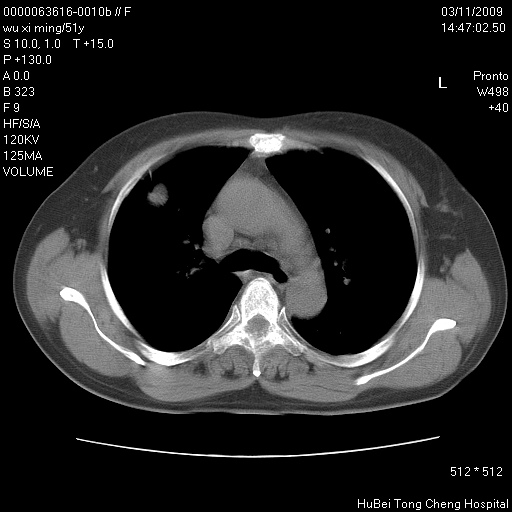

患者 女,51岁。因“胆囊炎,胆囊结石”,行常规术前胸部x线检查发现:右上肺结节病灶,建议行进一步检查。患者无咳嗽、咳痰及咯血等呼吸道症状,近期出现背部疼痛不适。

胸部ct轴位平扫(层厚10mm,螺距1.5,重建间隔10mm;部分层面:层厚3mm,螺距1.0,重建间隔3mm),图像如下:

右肺周围型肺癌伴肺内转移信胸椎转移

1、周围型肺癌。(毛刺正、血管束集征,分叶。)

集束征,胸膜牽拉征,毛刺,淺分葉高度提示ca.

右肺周围型肺癌伴肺内转移及胸椎转移。已无手术机会。